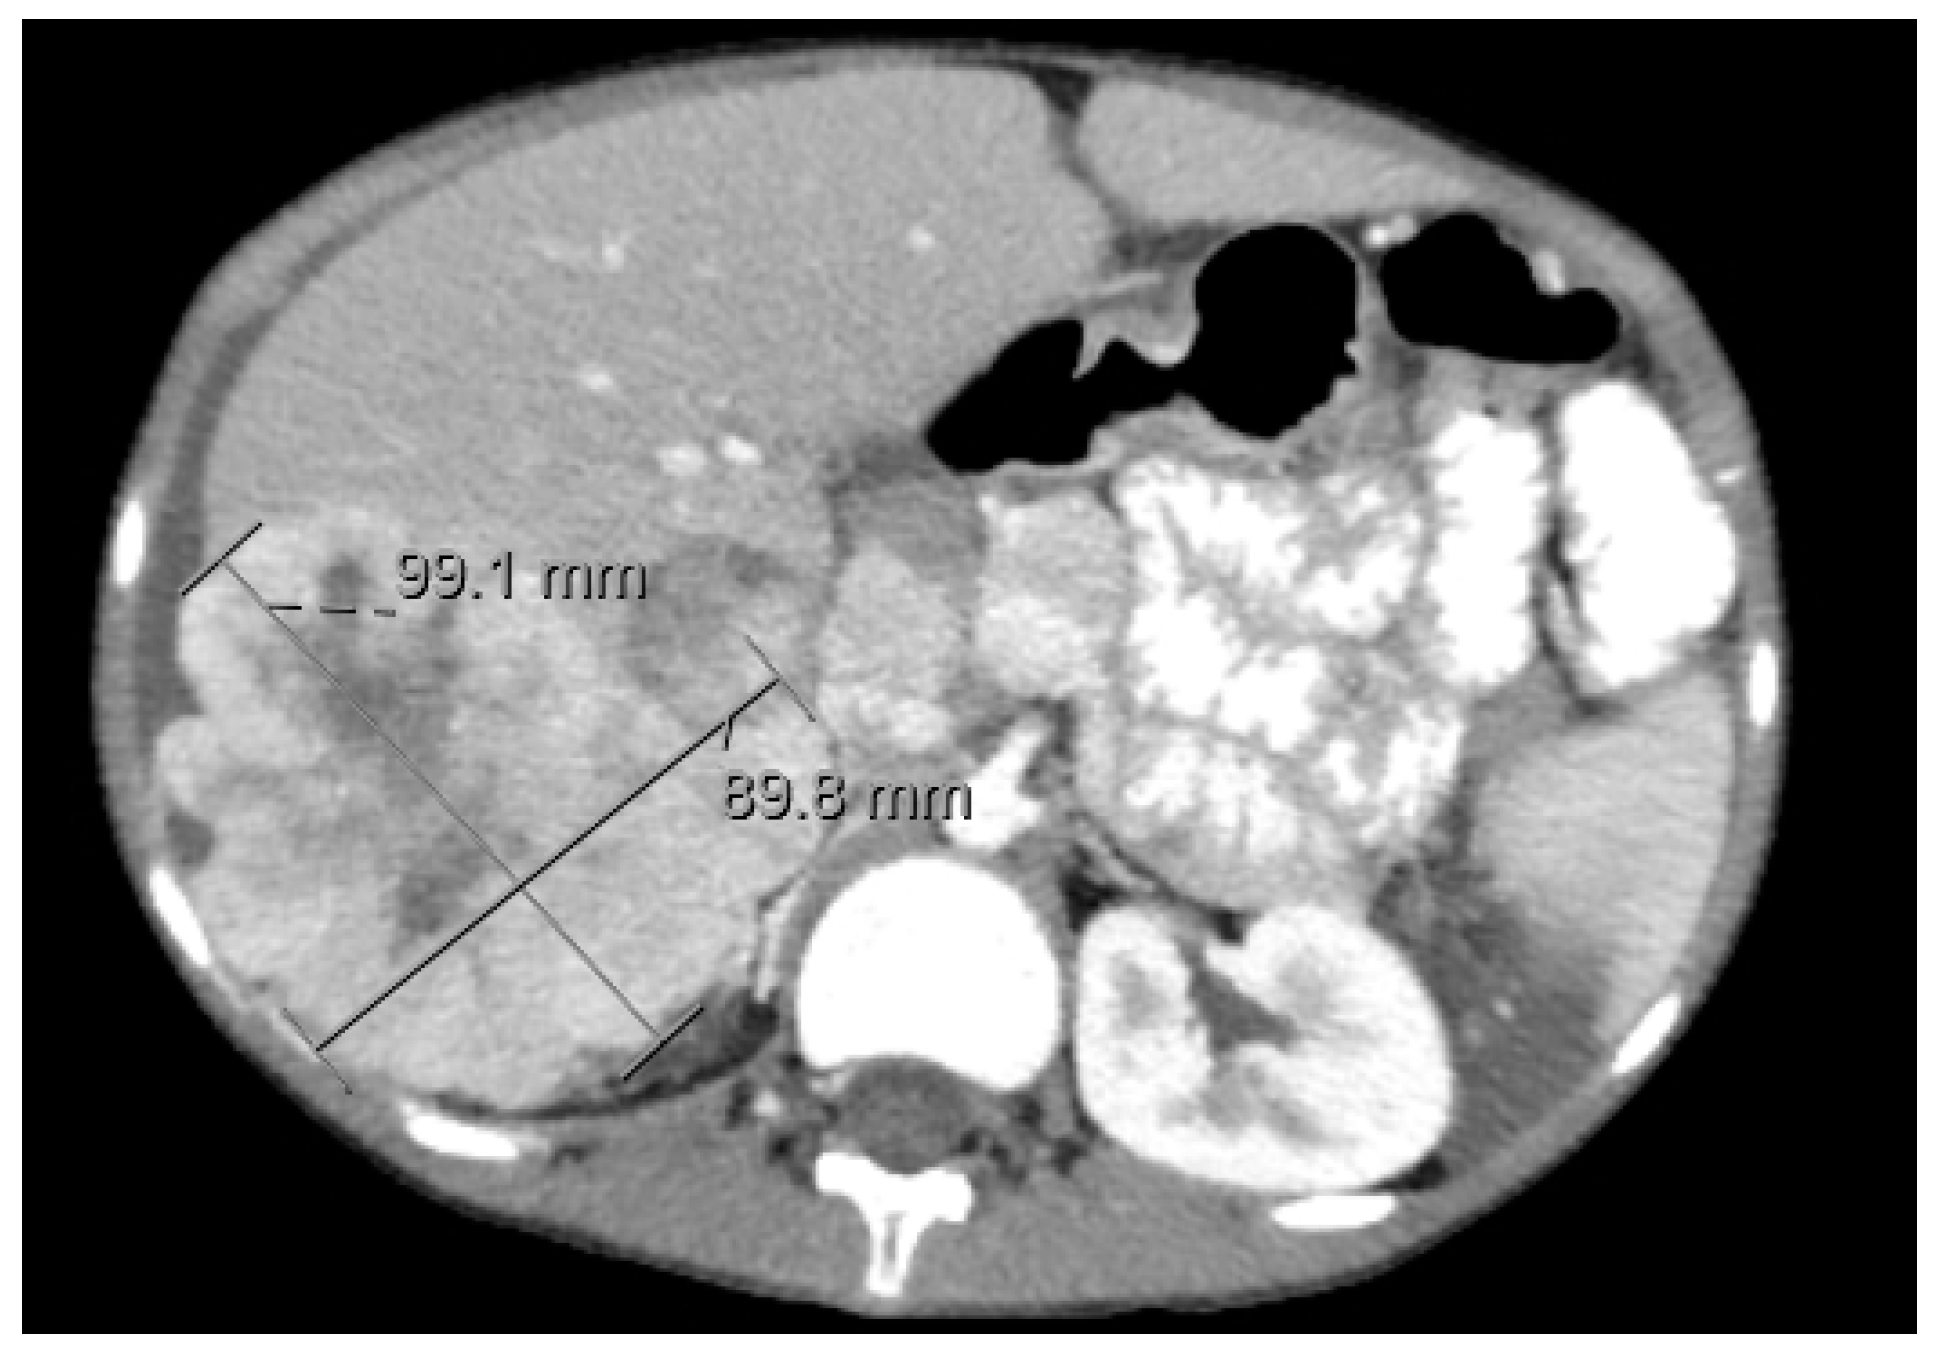

5.2.4. Diagnostic Imaging